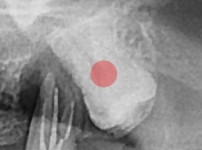

완전 매복 사랑니

조회

944

작성일

25-12-03